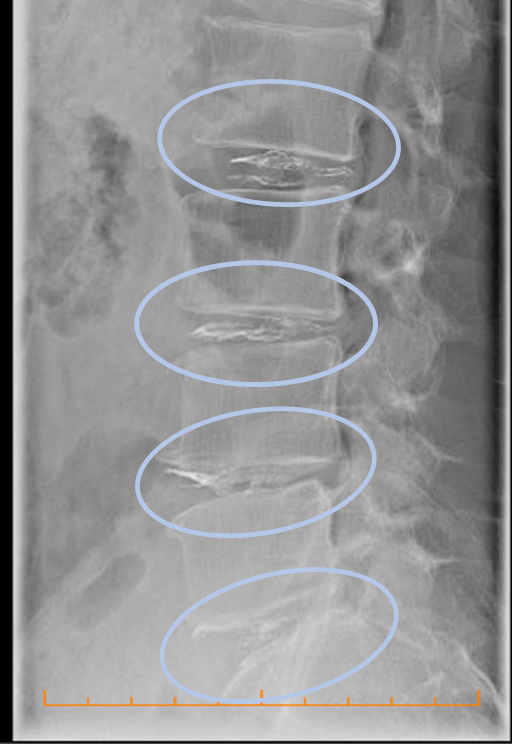

- Herniated discs were observed in L2/3, 3/4, 4/5.

The Cellgel method was performed in L2/3, 3/4, 4/5, and 5/s.

The Discogel injected into the four intervertebral discs is clearly visible.